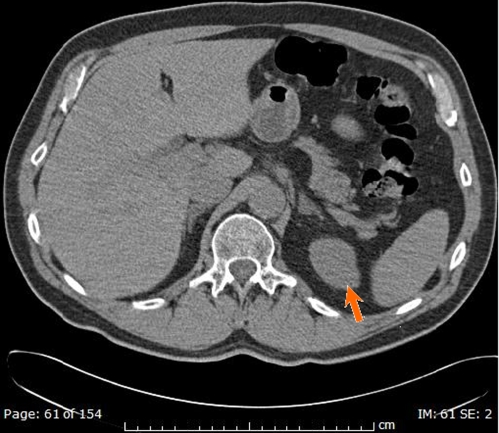

A repeat CT showed no change in the adrenal mass (Fig. 2).

Figure 2.

CT scan showing a left adrenal mass (arrow) measuring 1.5 cm.

The stable size over 4 years makes an adrenal malignancy unlikely. The biochemical evaluation remains most important in deciding how aggressively to evaluate an adrenal mass, particularly if it measures less than 4 cm.